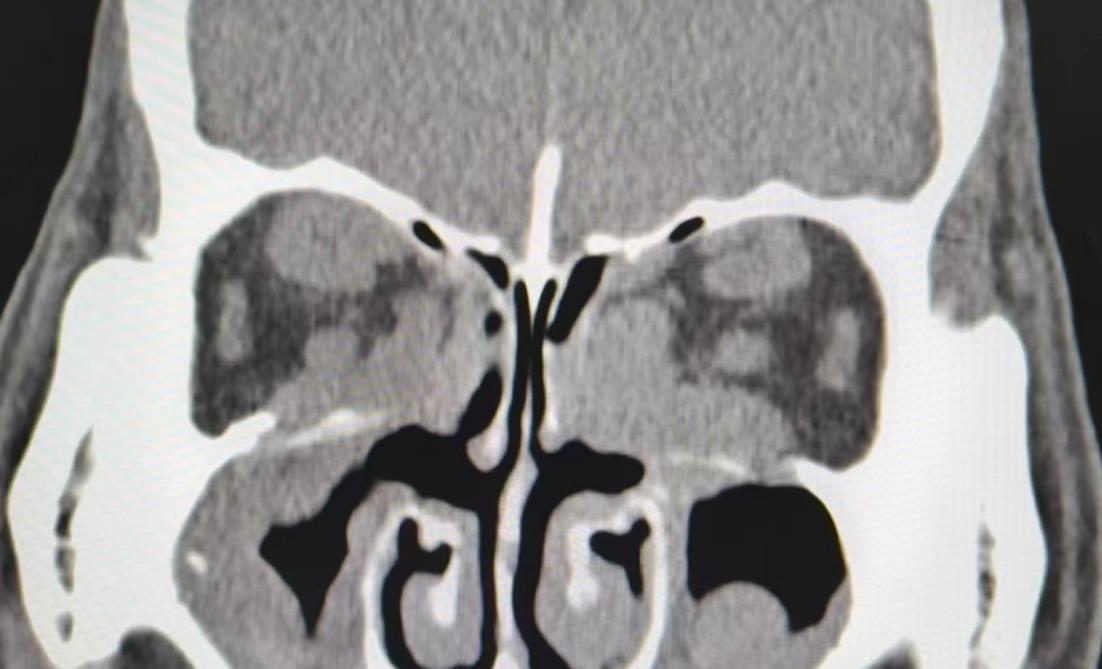

目的 评估内窥镜下经筛径路眶内壁减压(endoscopic transethmoidal orbital wall decompression, ETMOWD)联合脂肪减压(fat orbital decompression, FROD)术对甲状腺相关眼病(thyroid-associated ophthalmopathy, TAO)限制性斜视的影响效果。 方法 回顾性系列病例研究,选取2021年12月至2024年8月确诊为TAO的病例,按照是否行眶减压术,分成眶减压组(OD组)和非眶减压组(NOD组),比较两组之间围手术期的一般资料,斜视类型、眼球运动限制程度、眼肌后徙量及手术效果,并对OD组评估ETMOWD联合脂肪减压术式对斜视的影响。手术成功的定义为复视消失,术后斜视度≤ 5 PD。 结果 共计65 例纳入分析,其中OD组40例、NOD组25例,所有患者的甲状腺指标均在正常范围内,活动性评分均≤ 3分,处于静止期内,两组间的一般资料及术前斜视类型,包括水平和垂直斜视度差异无统计学意义(P > 0.05),而OD组眼球运动限制分级、手术次数、手术总肌肉数、水平肌肉数量以及水平肌肉后徙效应量明显高于NOD组,术后所有患者的眼球运动限制程度及复视情况均有明显缓解,ODG组治愈率为70%,NOD组治愈率为72%。并且,OD组经眶减压手术影响,眼压由术前的(19.43 ± 3.9) mmHg降至术后的(15.05 ± 2.2) mmHg(P < 0.001),而水平斜视度与垂直斜视度在术后均有所增加。 结论 与NOD相比,OD组斜视手术的复杂性增加,包括斜视程度、手术次数、总肌肉条数、水平肌条数及水平肌后徙效应量,ETMOWD联合脂肪减压术对水平肌的影响更为显著,但两种治疗方案的长期手术效果相似。

Objective To assess the efficacy of endoscopic transethmoidal orbital wall decompression (ETMOWD) in conjunction with fat removal orbital decompression (FROD) on restrictive strabismus in patients with thyroid?associated ophthalmopathy (TAO). Methods A retrospective case series study was conducted involving patients diagnosed with TAO at our hospital from December 2021 to August 2024. Patients were divided into two groups: the orbital decompression group (OD group) and the non?orbital decompression group (NOD group), based on whether they underwent orbital decompression surgery. The study compared perioperative data, types of strabismus, degree of ocular motility limitation, extent of posterior migration of ocular muscles, and postoperative outcomes between the two groups. Additionally, the effects of ETMOWD combined with FROD on strabismus were evaluated by analyzing changes in relevant indices before and after surgery in the OD group. Results A total of 65 participants were included in the analysis, with 40 in the OD group group and 25 in the NOD group. There was no statistically significant difference in baseline characteristics between the two groups. Preoperative strabismus types, including horizontal and vertical strabismus, did not differ significantly between the OD and NOD groups (P > 0.05). However, the mean preoperative restriction grade of eye movement was significantly higher in the OD group compared to the NOD group. Additionally, the number of surgeries, mean total operated muscles, and number of horizontal muscles were all significantly higher in the OD group than in the NOD group (all P < 0.05), with a notably different effect on horizontal muscle migration between the two groups. The degree of restriction of eye movement and diplopia improved significantly in all patients, with cure rates of 70% in the OD group and 72% in the NOD group. Furthermore, the OD group underwent ETMOWD combined with FROD orbital decompression surgery, which resulted in a decrease in intraocular pressure (IOP) from (19.43 ± 3.9) mmHg preoperatively to (15.05 ± 2.2 mmHg postoperatively (P < 0.001). Both horizontal and vertical strabismus increased after surgery. Conclusions Our results demonstrated that, compared with the NOD group, the OD group exhibited increased complexity in strabismus surgery, as evidenced by a higher number of operations, total muscle strips, horizontal muscle strips, and greater migratory effect size of the horizontal muscles. The combination of ETMOWD and FROD effectively reduced exophthalmos, with a more pronounced effect on the medial rectus muscle compared to the vertical muscles. However, the long?term outcomes between the two groups were similar.